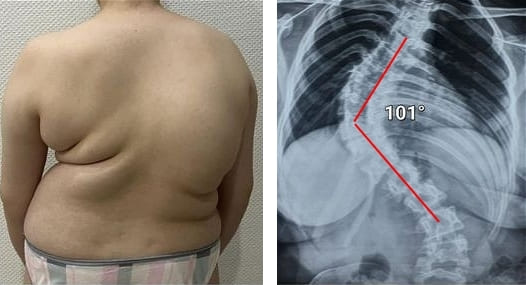

Quyidagi suratlarga qarang. Belgilarga e’tibor bermaganlarning boshiga nimalar tushganini ko‘ring. Bugun bu odamlar umidsiz holatda, ularning ko‘pchiligida yordam so‘rashga ham odam qolmagan. Siz ham o‘zingizga bunday taqdirni ravo ko‘rasizmi?

52 yoshli ayol. Orqa umurtqa diskining siljishi va og‘ir deformatsiyasi, asablar siqilishi va orqa miyaga shikast yetgan.

Ayol, 51 yosh. Bukrilik va umurtqa deformatsiyasi. “Joint Solve” kursidan so‘ng bukrilik to‘liq yo‘qoldi.